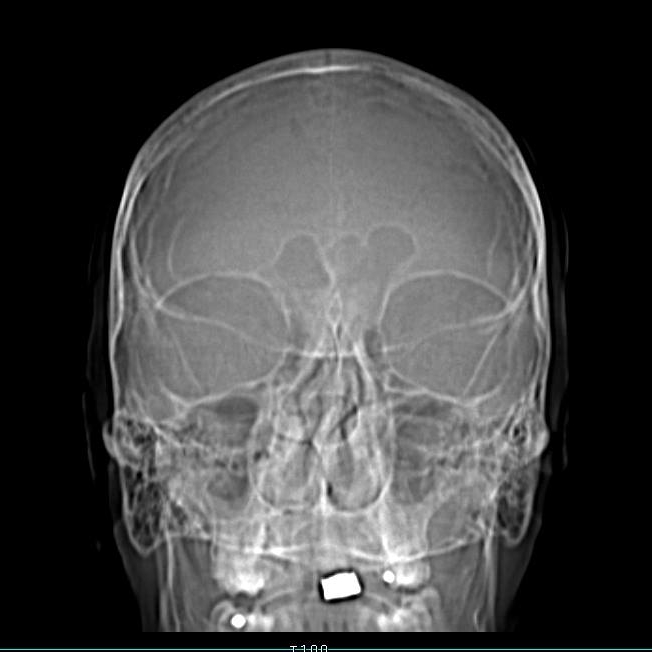

I thought I was just prone to headaches but my Doctor kept wanting to treat me for allergies. I got a cat-scan and saw where my sinuses were in my forehead and realized that when I had a headache, I could outline my sinuses with a sharpie as the place where the pain was coming from. That area that looks like a paw print between my eyes.

No massive tumor – just the tiny swollen sinuses – geeeee whiz